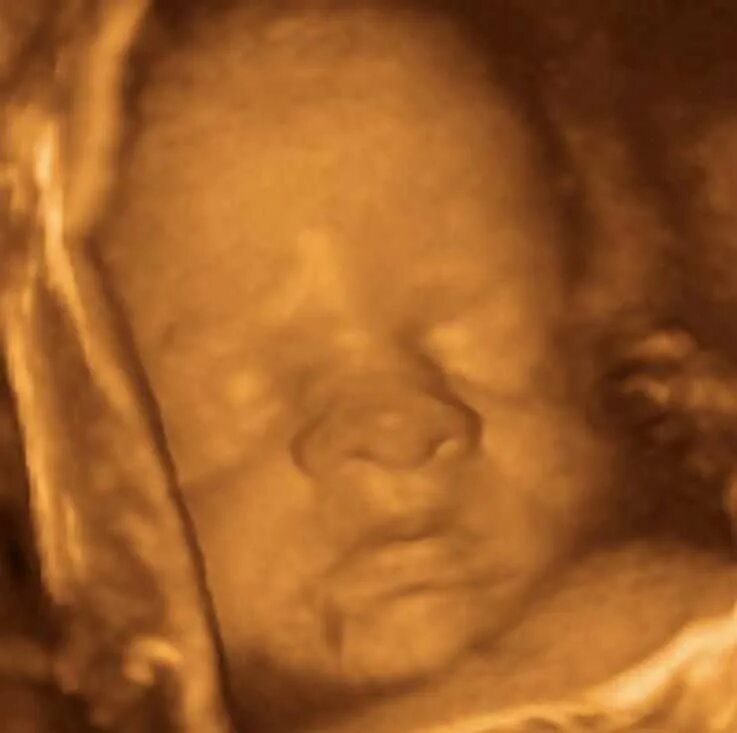

Развития плода 30 недель